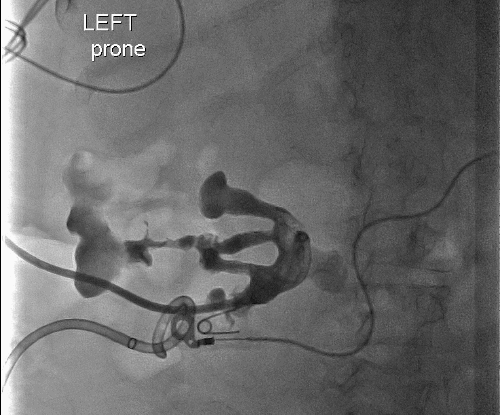

The patient's left nephrostomy output decreased over time, and a renal scan was performed to evaluate for renal function, which revealed the same findings as prior imaging (Figure 3). On hospital day 24, the decision was made to take the patient to the operating room. She underwent a total left nephrectomy, fistula takedown, descending colon debridement, colotomy closure, and debridement of the subcutaneous wound. The colon was left alone until the nephrectomy was completed. At this time, the colon was exteriorized through the extraction incision in the left lower abdomen. The colon around the fistula was sharply debrided with a scalpel, and the colotomy was closed in a vertical fashion with a running 2-0 Vicryl to prevent any stricturing. The primary repair was then imbricated with 3-0 silk sutures. In the left flank, a large pocket of infected necrotic tissue was debrided, removed, and sent for culture. The wound was irrigated, and a size 10 Jackson-Pratt (JP) drain was left to drain the space. The patient tolerated the procedure well and was discharged to subacute rehab on postoperative day 6 (hospital day 30). Her drains had been removed prior to discharge, and she was placed on oral antibiotics. She was doing well on follow-up and regaining her strength at the rehabilitation facility.

Figure 3. Left Nephrostomy Tube in Good Position and Widely Patent. Published with Permission

Poor output likely secondary to obstructive nature of staghorn calculus with isolated infundibulum